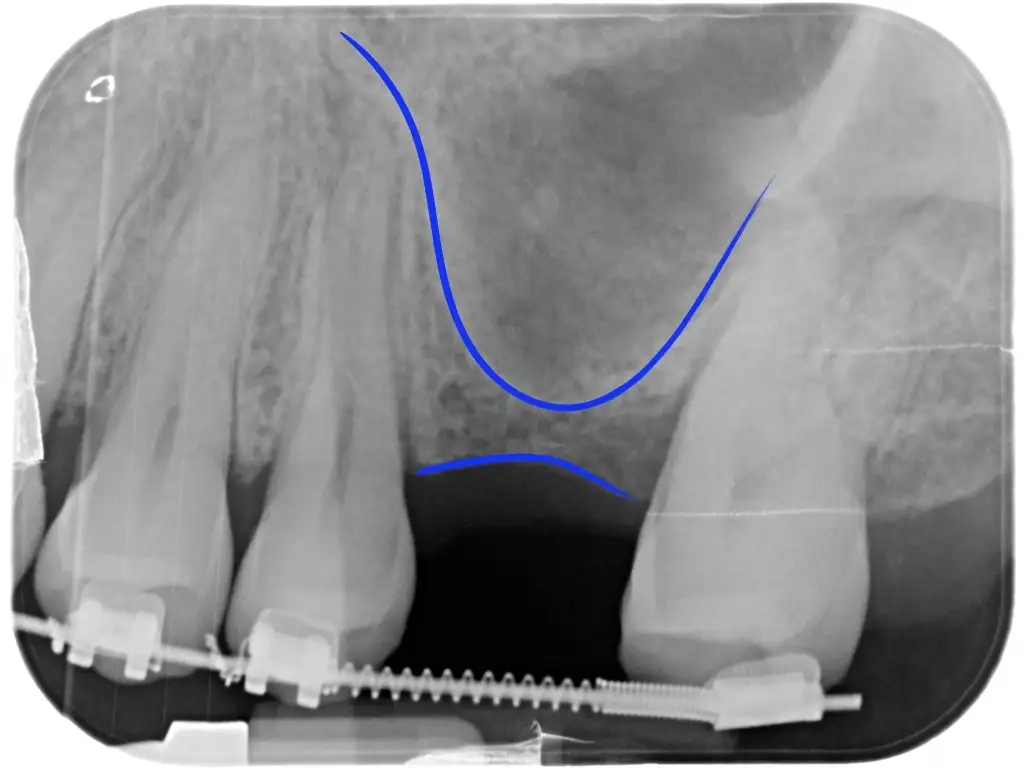

Fra le tecniche rigenerative è quella che probabilmente è necessaria più spesso. Al di sopra dei molari e premolari superiori è presente il seno mascellare. Questa è una cavità che, come gli altri seni paranasali, è vuota e piena d’aria (quando in salute), coperta da una sottile mucosa e in comunicazione con il naso.

E’ una cavità abbastanza ampia e spesso a diretto contatto con le radici dei molari. Quando un dente posteriore viene perso capita spesso che l’osso rimanente sia molto poco in altezza e impedisca di posizionare un impianto di lunghezza sufficiente.

Il seno mascellare fa part dei seni paranasali, si trova sopra le radici dei denti posteriori. Quando mancano i denti molto spesso l’altezza ossea è insufficiente a posizionare un impianto